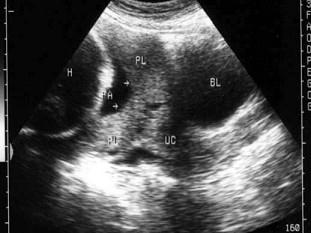

问题 女,25岁,停经37周,阴道不规则出血来院就诊,B超检查声像图如图所示,最可能的诊断为?(?)

选项 A.胎盘早剥 B.前置胎盘 C.副胎盘 D.胎膜破裂 E.以上都不是

答案 B